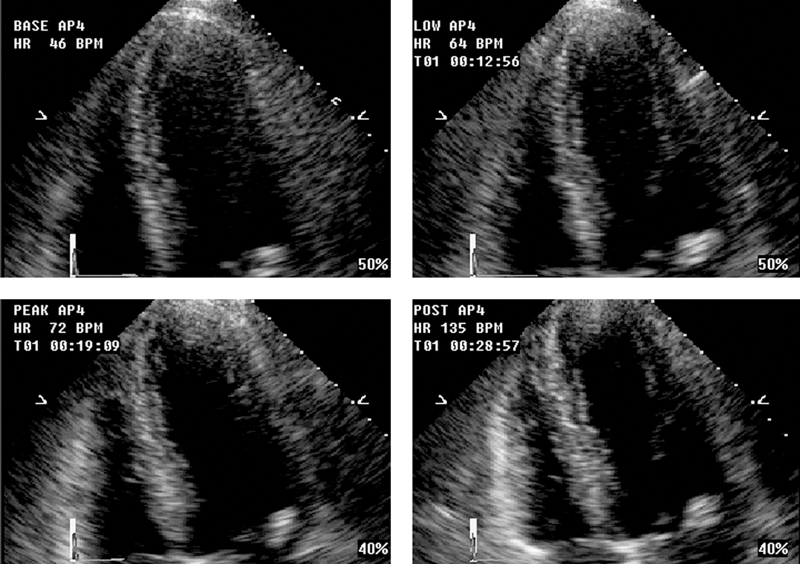

فحوصات تشخيصية لبعض امراض القلب والشرايين التاجية